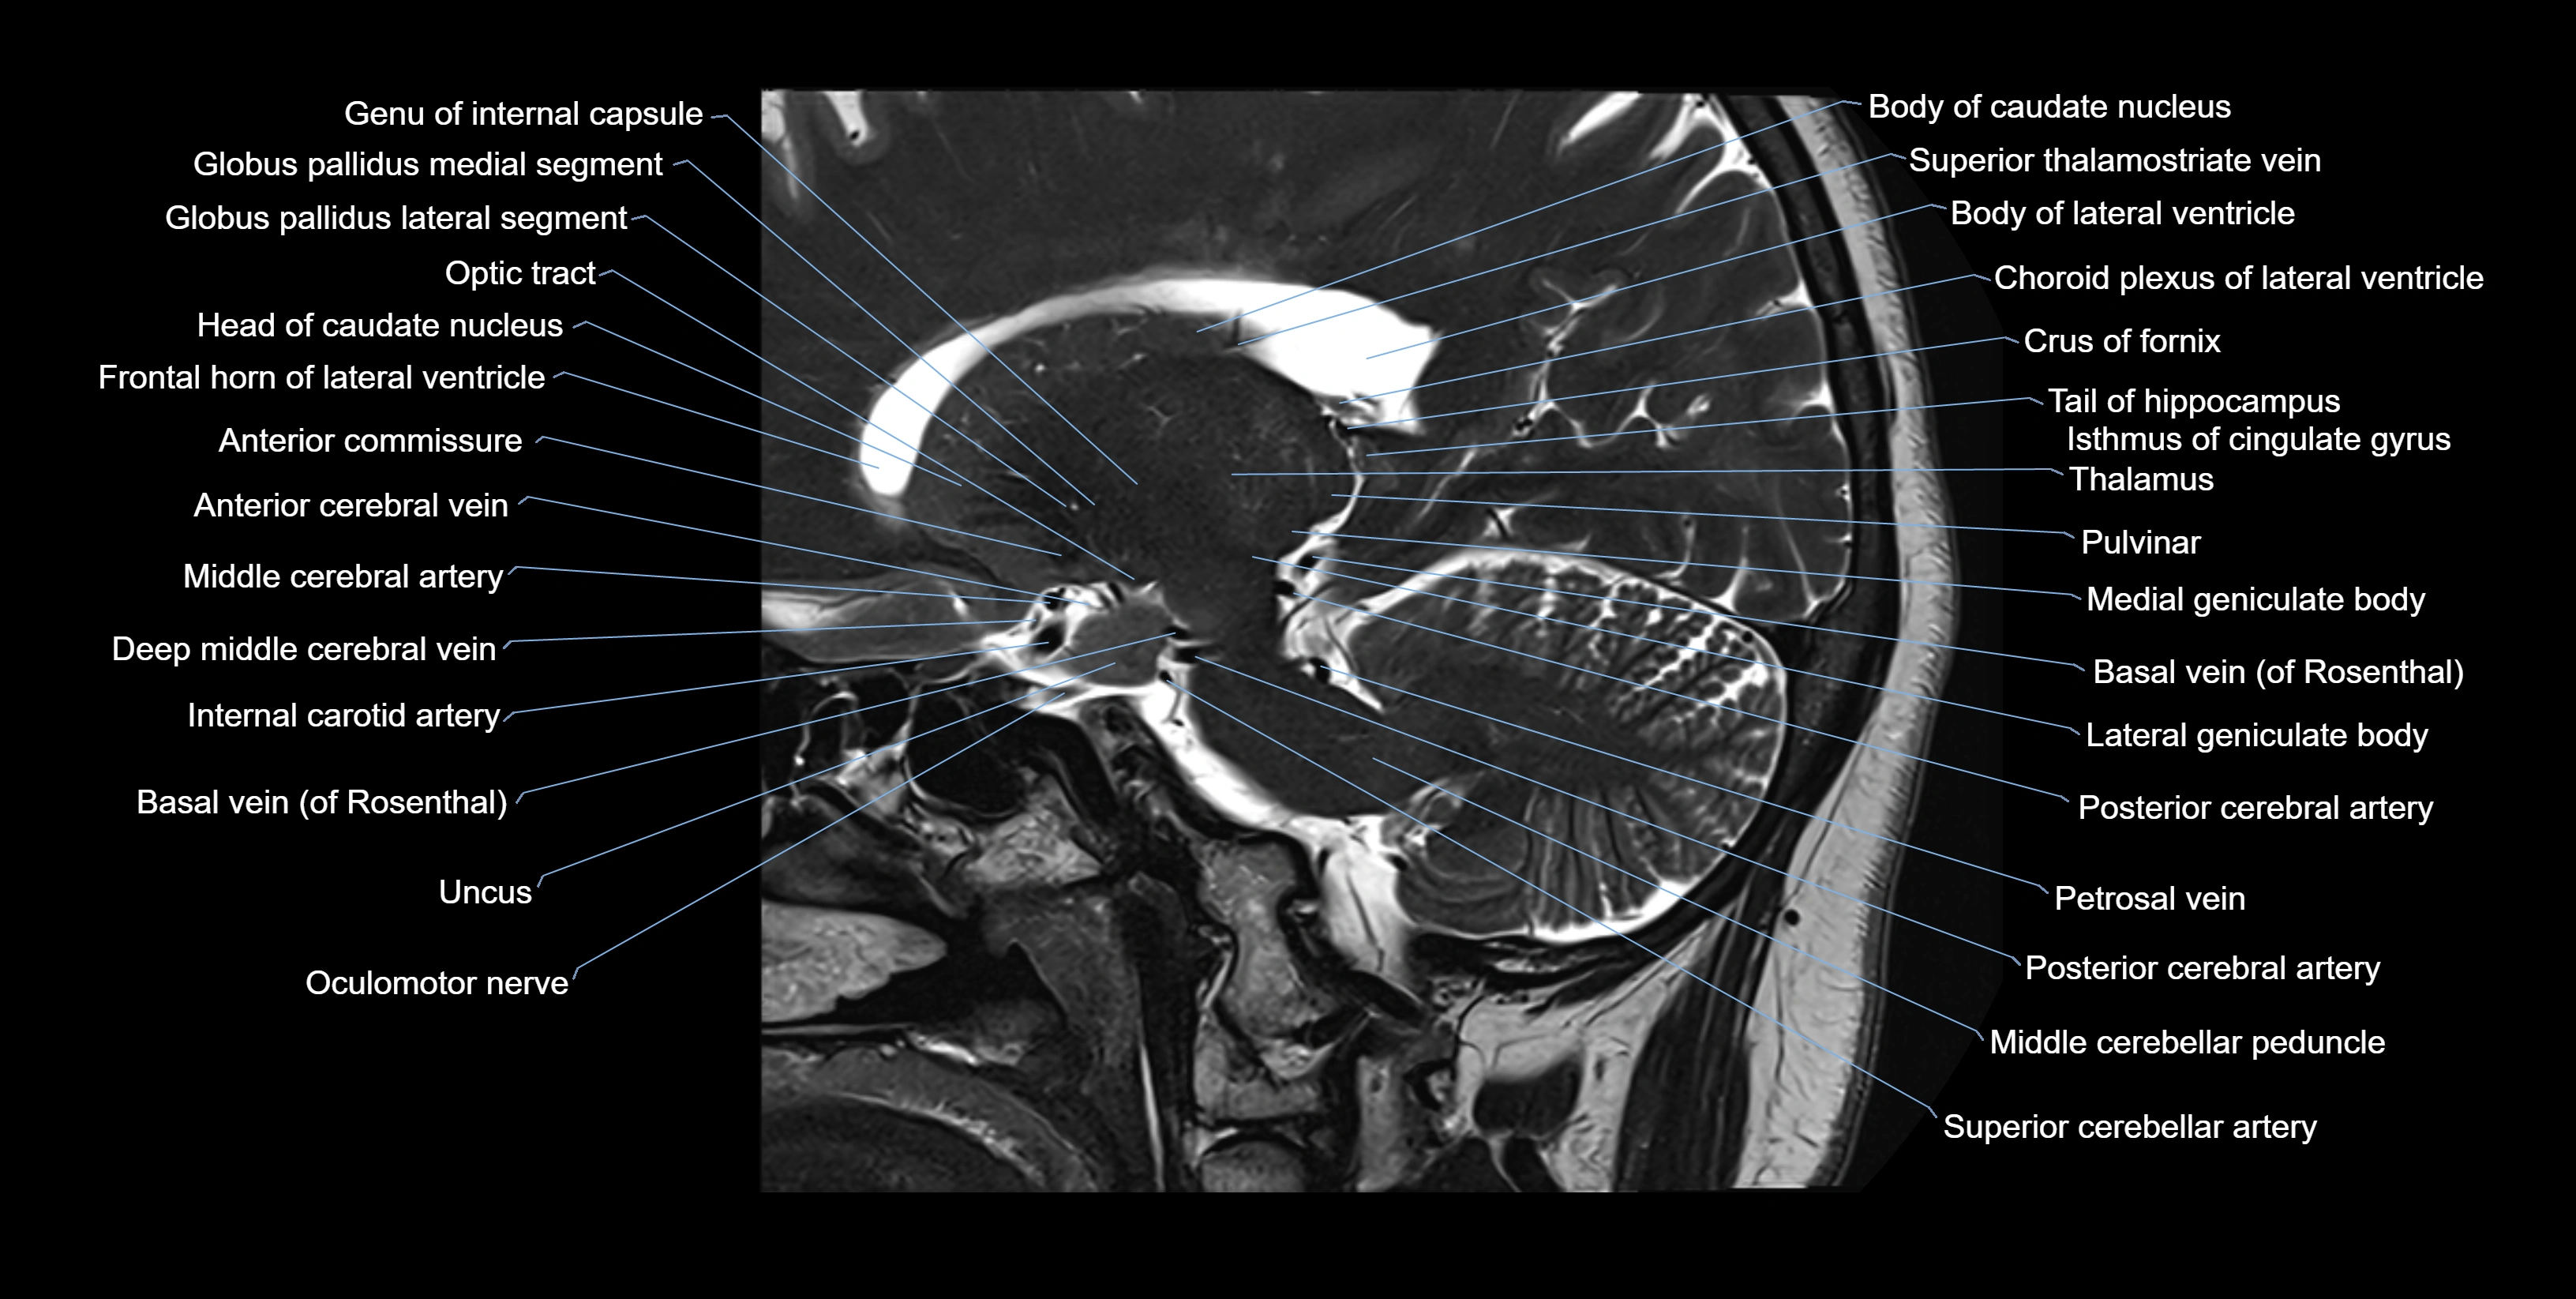

MRI images

image